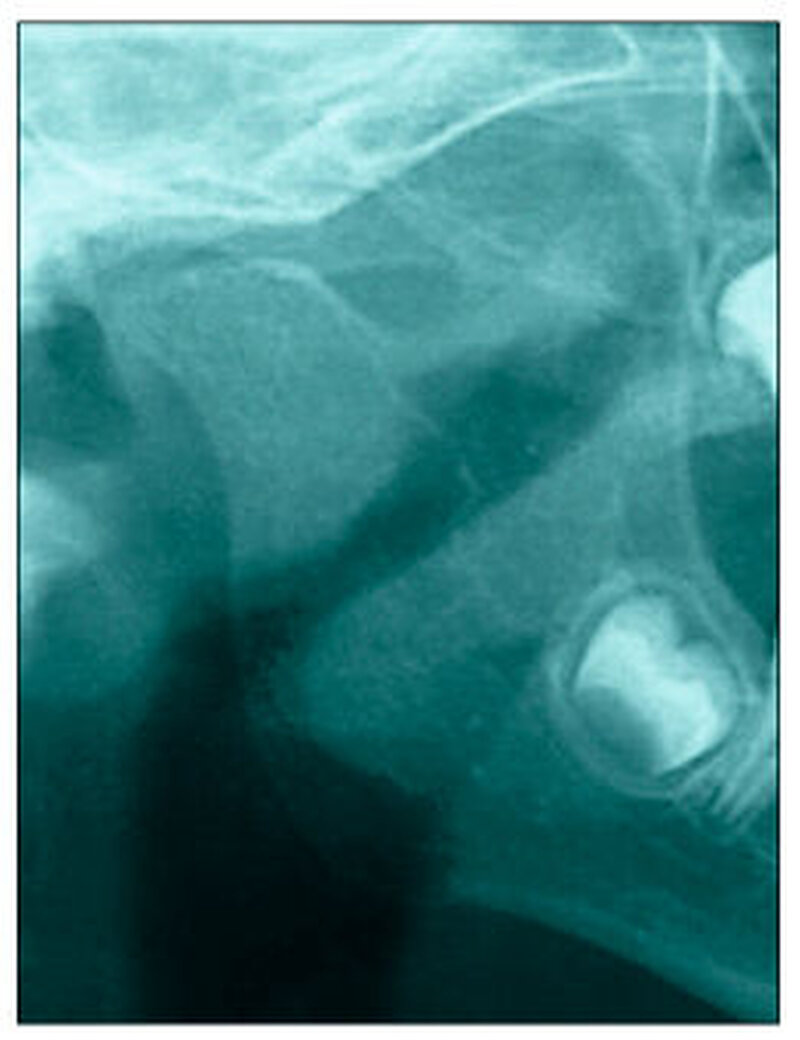

Bereits 2004 wies Carla Evans [Evans, 2005] auf das Risikomanagement bei Allgemeinerkrankungen hin und stellte am Beispiel der JIA dar, dass Unterkieferrücklagen und frontal offene Bisse aus der Kiefergelenkzerstörung entstehen können. Die Röntgenaufnahmen einer JIA-Patientin mit oligoartikulärer Form und Beteiligung des rechten Kiefergelenkes zeigen den typischen Verlauf sehr gut. Bei ursprünglich sehr dezenten Befunden, wie einer s-förmigen Mundöffnung von 44 mm, einer geringen Mittenabweichung um 2 mm nach rechts und einem frontal offenem Biss klagte sie über Schmerzen beim Essen, was den Anlass zur weiteren Diagnostik bot. Die erste Panoramaröntgenschichtaufnahme (Abbildung 1a-c) zeigt auf der rechten Seite einen abgeflachten Kondylus und eine bereits verstrichene Fossa condylaris. Ein Jahr später vermittelt das Fernröntgenseitenbild (Abbildung 1d) trotz fortschreitender kondylärer Resorption ein harmonisches Bild, während nach drei Jahren bei voranschreitendem Abbau des rechten Kondylus (Abbildung 1e) eine Rücklage der Mandibula und eine Bissöffnung manifest sind (Abbildung 1f).

Bei 152 durchschnittlich 12-jährigen Rheumapatienten wurden die kondyläre Morphologie und Symmetrie beziehungsweise Asymmetrie im Vergleich zu einer Kontrollgruppe anhand der OPG analysiert. Zur Analyse erfolgte die Zuordnung zu vier morphologischen Graden je Kondylus (Abbildung 3a-d). Bei 45 Prozent der Rheumapatienten waren morphologische Veränderungen im Rahmen kondylärer Resorption unterschiedlicher Ausprägung zu finden. Die „Kontrollpatienten“ ohne JIA zeigten nur zu 14 Prozent formatypische Kondylen. Der Unterschied zwischen den beiden Gruppen war signifikant. Daher sollte bei der Routineauswertung von Panoramaröntgenschichtaufnahmen auf diese Anzeichen geachtet werden, insbesondere auch unter dem Aspekt, dass laut Assaf [2011] durchschnittlich 4,3 Jahre zwischen Erstmanifestation der JIA und Erstvorstellung in der Rheumasprechstunde des UKE liegen.